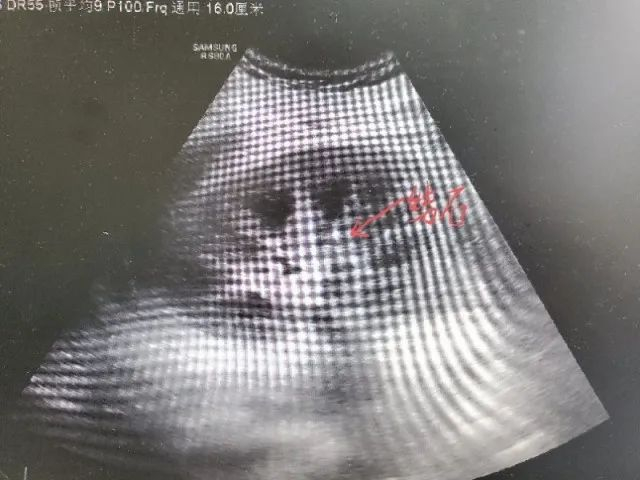

“正常人每天的尿量应该在2000至3000毫升。”考虑到小柯病情严重,赵宁当机立断为他进行了血液透析治疗,帮助肾脏清除体内毒素。进一步肾穿刺活检后,医生惊奇发现,小柯多处肾小管内存在钙化样物,超声显示双肾存在多发结石。